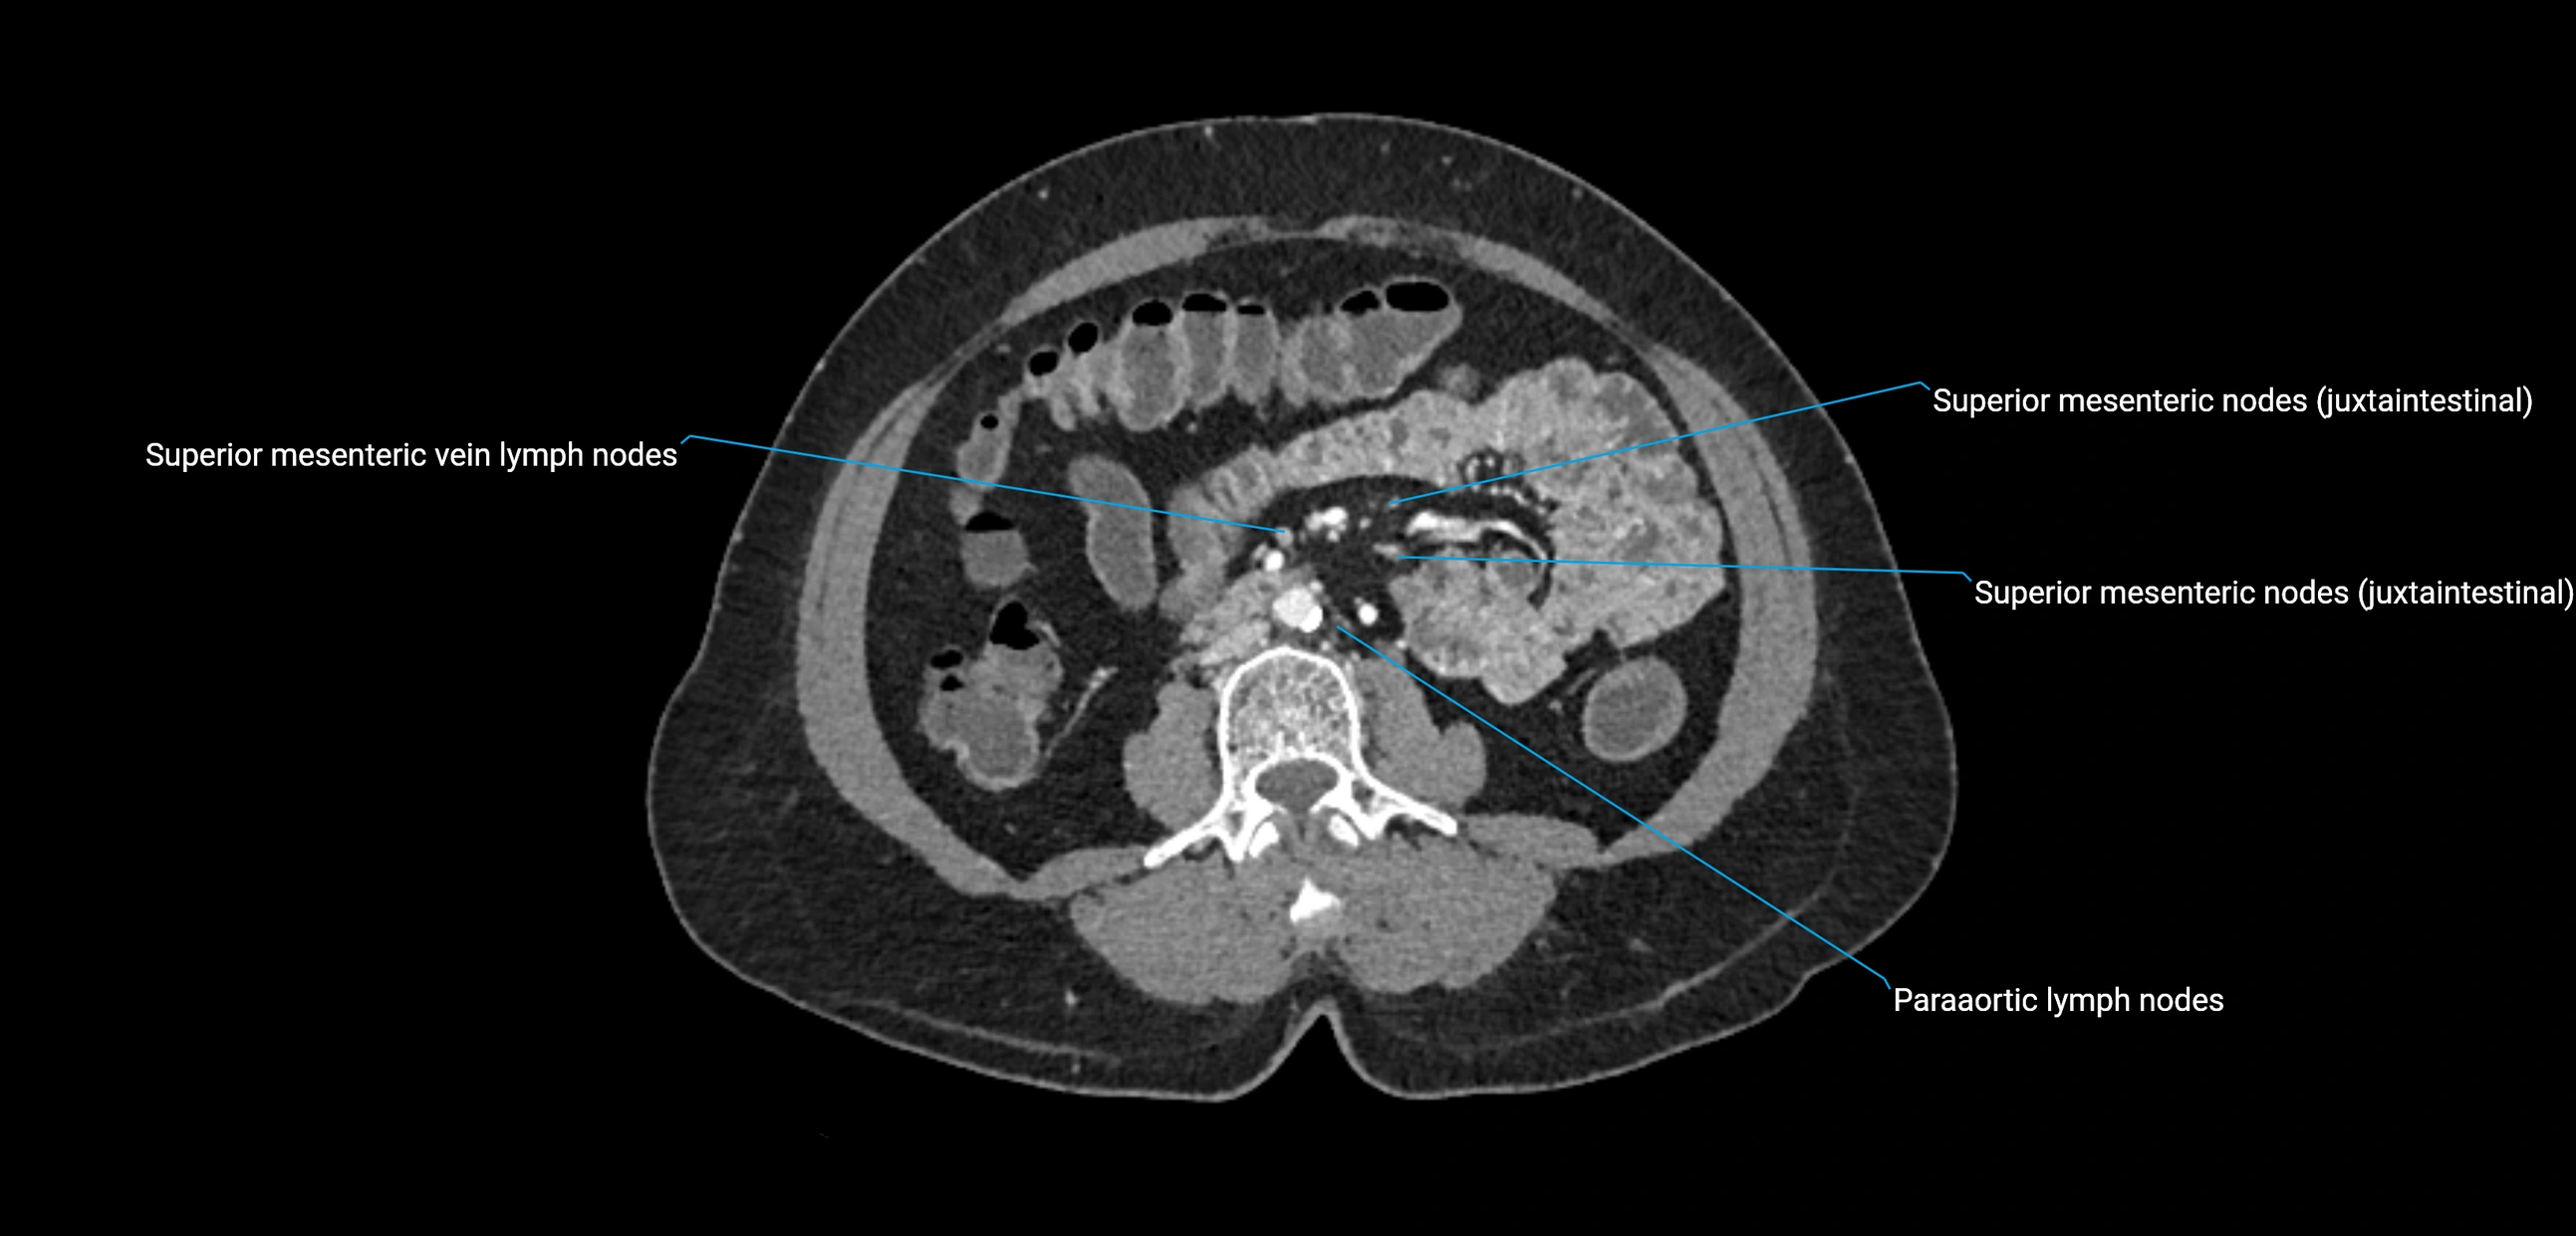

CT Appearance

CT Pre-Contrast:

• Nodes appear as soft-tissue density nodules adjacent to the aorta and IVC

• Calcification may be seen in chronic infections (e.g., tuberculosis)

CT Post-Contrast:

• Normal nodes enhance homogeneously

• Malignant nodes may show heterogeneous enhancement, central necrosis, or conglomerate formation

• Size >1 cm short axis is suspicious, though morphology and distribution are equally important